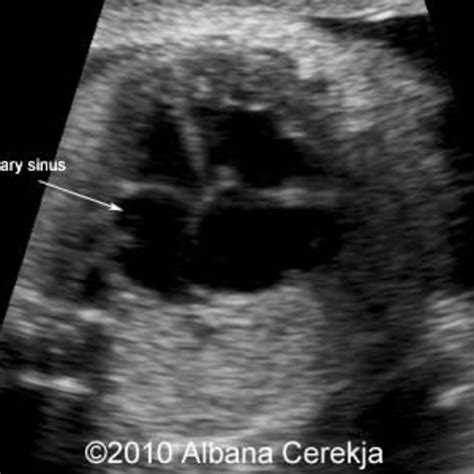

• Echocardiography: Transthoracic or transesophageal echocardiography can sometimes identify an LSVC, particularly if it is associated with other congenital heart defects. However, its sensitivity for detecting isolated LSVC is limited.